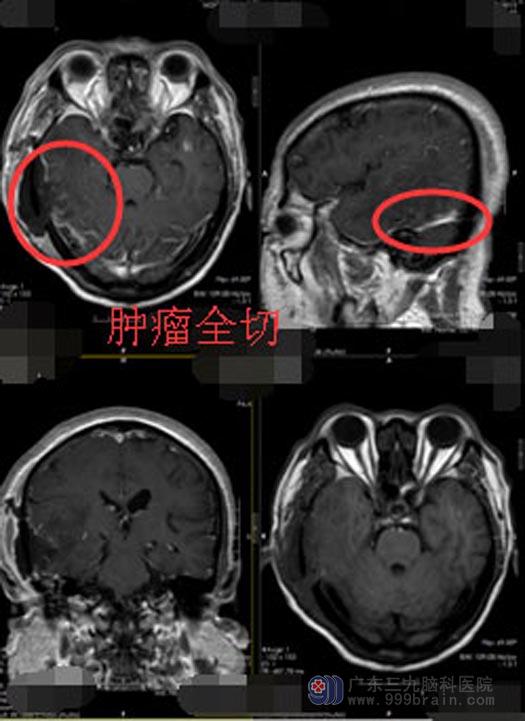

急坏了家人带着余老伯跑了多家知名的三甲医院,可得到的答复不是床位紧张就是医院条件有限。后来通过朋友的推荐,最终来到广东三九脑科医院神经外五科。进一步头颅CT检查提示:右侧颞叶占位,考虑脑膜瘤。完善术前检查后,医院副院长、神经外五科主任鲁明带领团队迅速为余老伯制定了手术方案,决定在导航下行“右侧颞叶肿瘤切除术”。手术进行得十分顺利;术后第三天,余老伯就可以下床活动、普通饮食;术后第十天,余老伯就康复出院了。

▲手术后